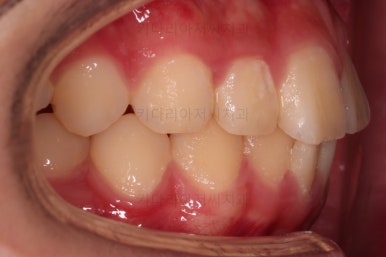

초진 때의 입안의 모습입니다.

집 근처 치과에서 어금니가 나와야 하는데 보이지 않는다는 말씀을 듣고 키다리아저씨치과로 찾아오셨어요.

치열이 조금 삐뚤긴 하지만 교정치료는 크게 관심 없었던 환자분이었습니다.

밥 먹는 것도 크게 불편함이 없었고요.

옆모습은 양호했고요.

웃을 때 드러나는 치열이 약간 삐뚤었지만 교정치료는 원하지 않으셨습니다.